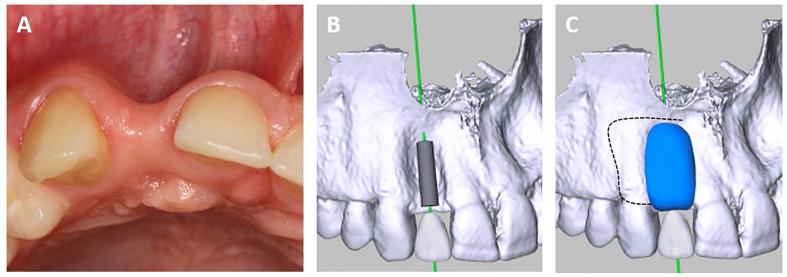

CBCT-scans of a 19-year-old male treated with an allogeneic bone block were recorded pre-OP, post-OP, and following six months of healing. Graft shrinkage was assessed via two image matching tools, namely coDiagnostiX® and Slicer. A biopsy specimen was harvested along the implant canal at the time of implantation.

The osseous defect was successfully restored and advanced graft remodelling was found upon re-entry as confirmed by the histomorphometric and histologic analysis. The initial volumes of the graft determined via coDiagnostiX® and Slicer were 0.373 mL and 0.370 mL., respectively, while graft resorption after six months of healing was 0.011 mL (3.00%) and 0.016 mL (4.33%).

对一名接受同种异体骨块治疗的19岁男性患者在术前、术后及愈合6个月后进行CBCT扫描。通过两种图像匹配工具coDiagnostiX®和Slicer评估移植物收缩情况。在植入时沿种植体通道采集活检标本。

骨缺损成功修复,再次切开时发现移植物有明显的重塑,组织形态计量学和组织学分析证实了这一点。通过coDiagnostiX®和Slicer测定的移植物初始体积分别为0.373 mL和0.370 mL,而愈合6个月后的移植物吸收量分别为0.011 mL(3.00%)和0.016 mL(4.33%)。